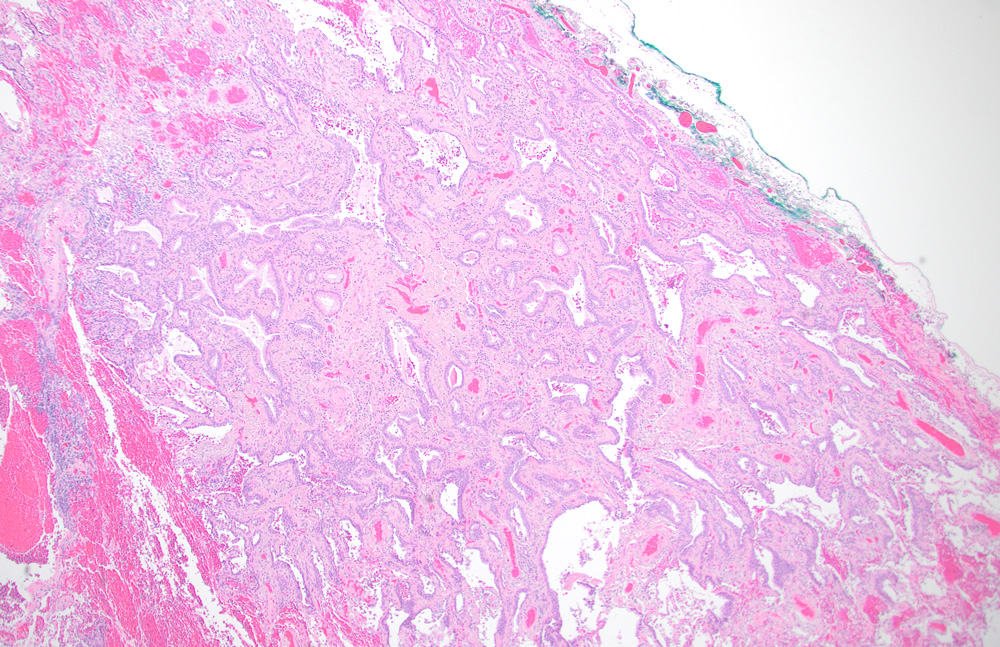

Histologic examination of this nodule revealed a subpleural 0.4 cm tumor (Figure 1). The tumor was composed of glands covered by bilayered (luminal and basal) epithelium. The luminal cells were comprised of a mixture of ciliated columnar cells and mucus cells (Figure 2).